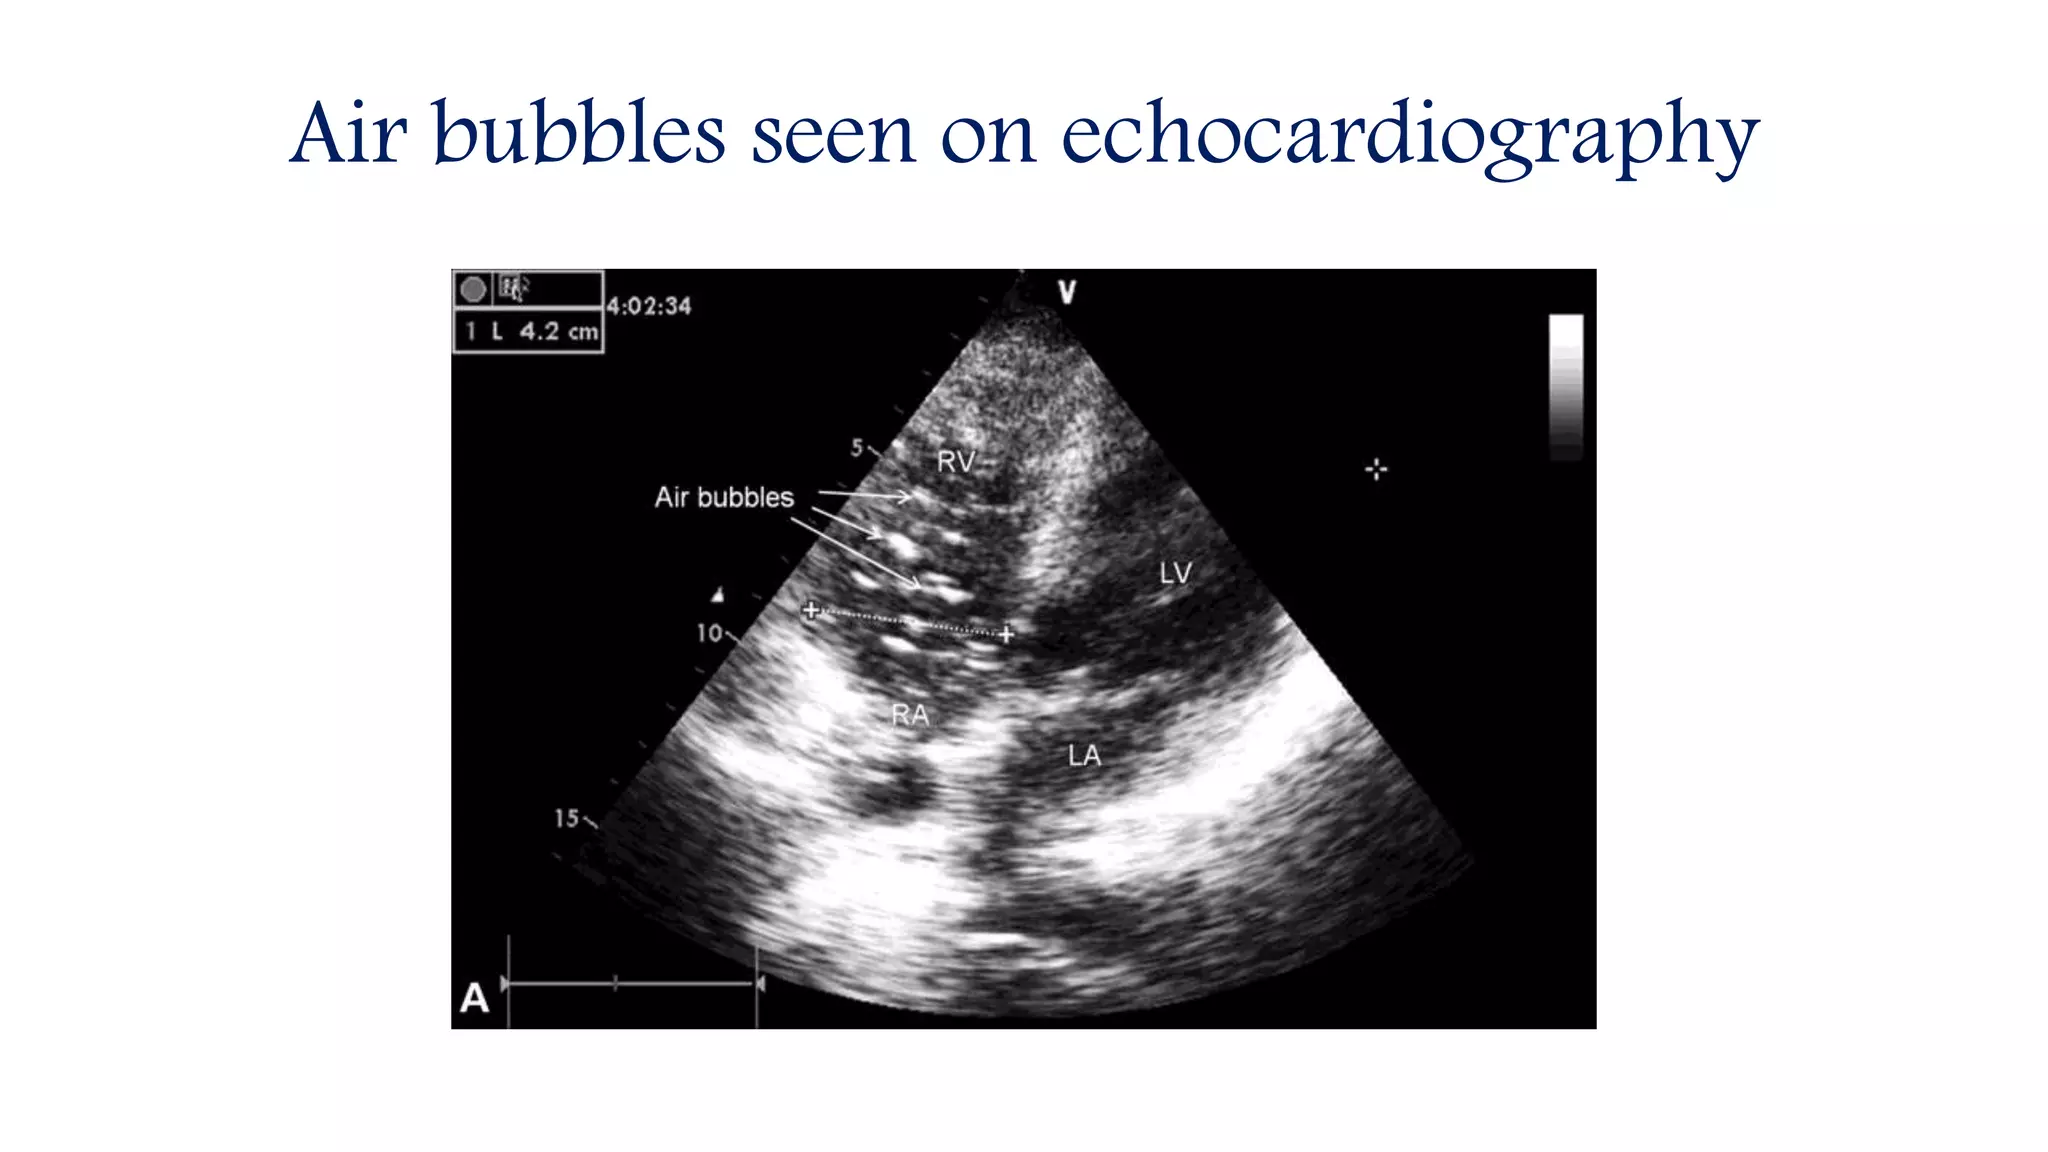

Air bubbles seen on echocardiography

• Active root venting upon termination of bypass is mandatory

to evacuate any ejected air, but it is not uncommon for some air to

pass down the right coronary artery or an aortocoronary venous

bypass graft and cause right ventricular dysfunction upon weaning

from bypass.

• This problem usually resolves quickly, but bypass should be

reinstituted if hemodynamics are compromised.

• TEE monitoring is the best means of identifying retained air as the

heart is weaned from bypass.

Air bubbles seen on TEE